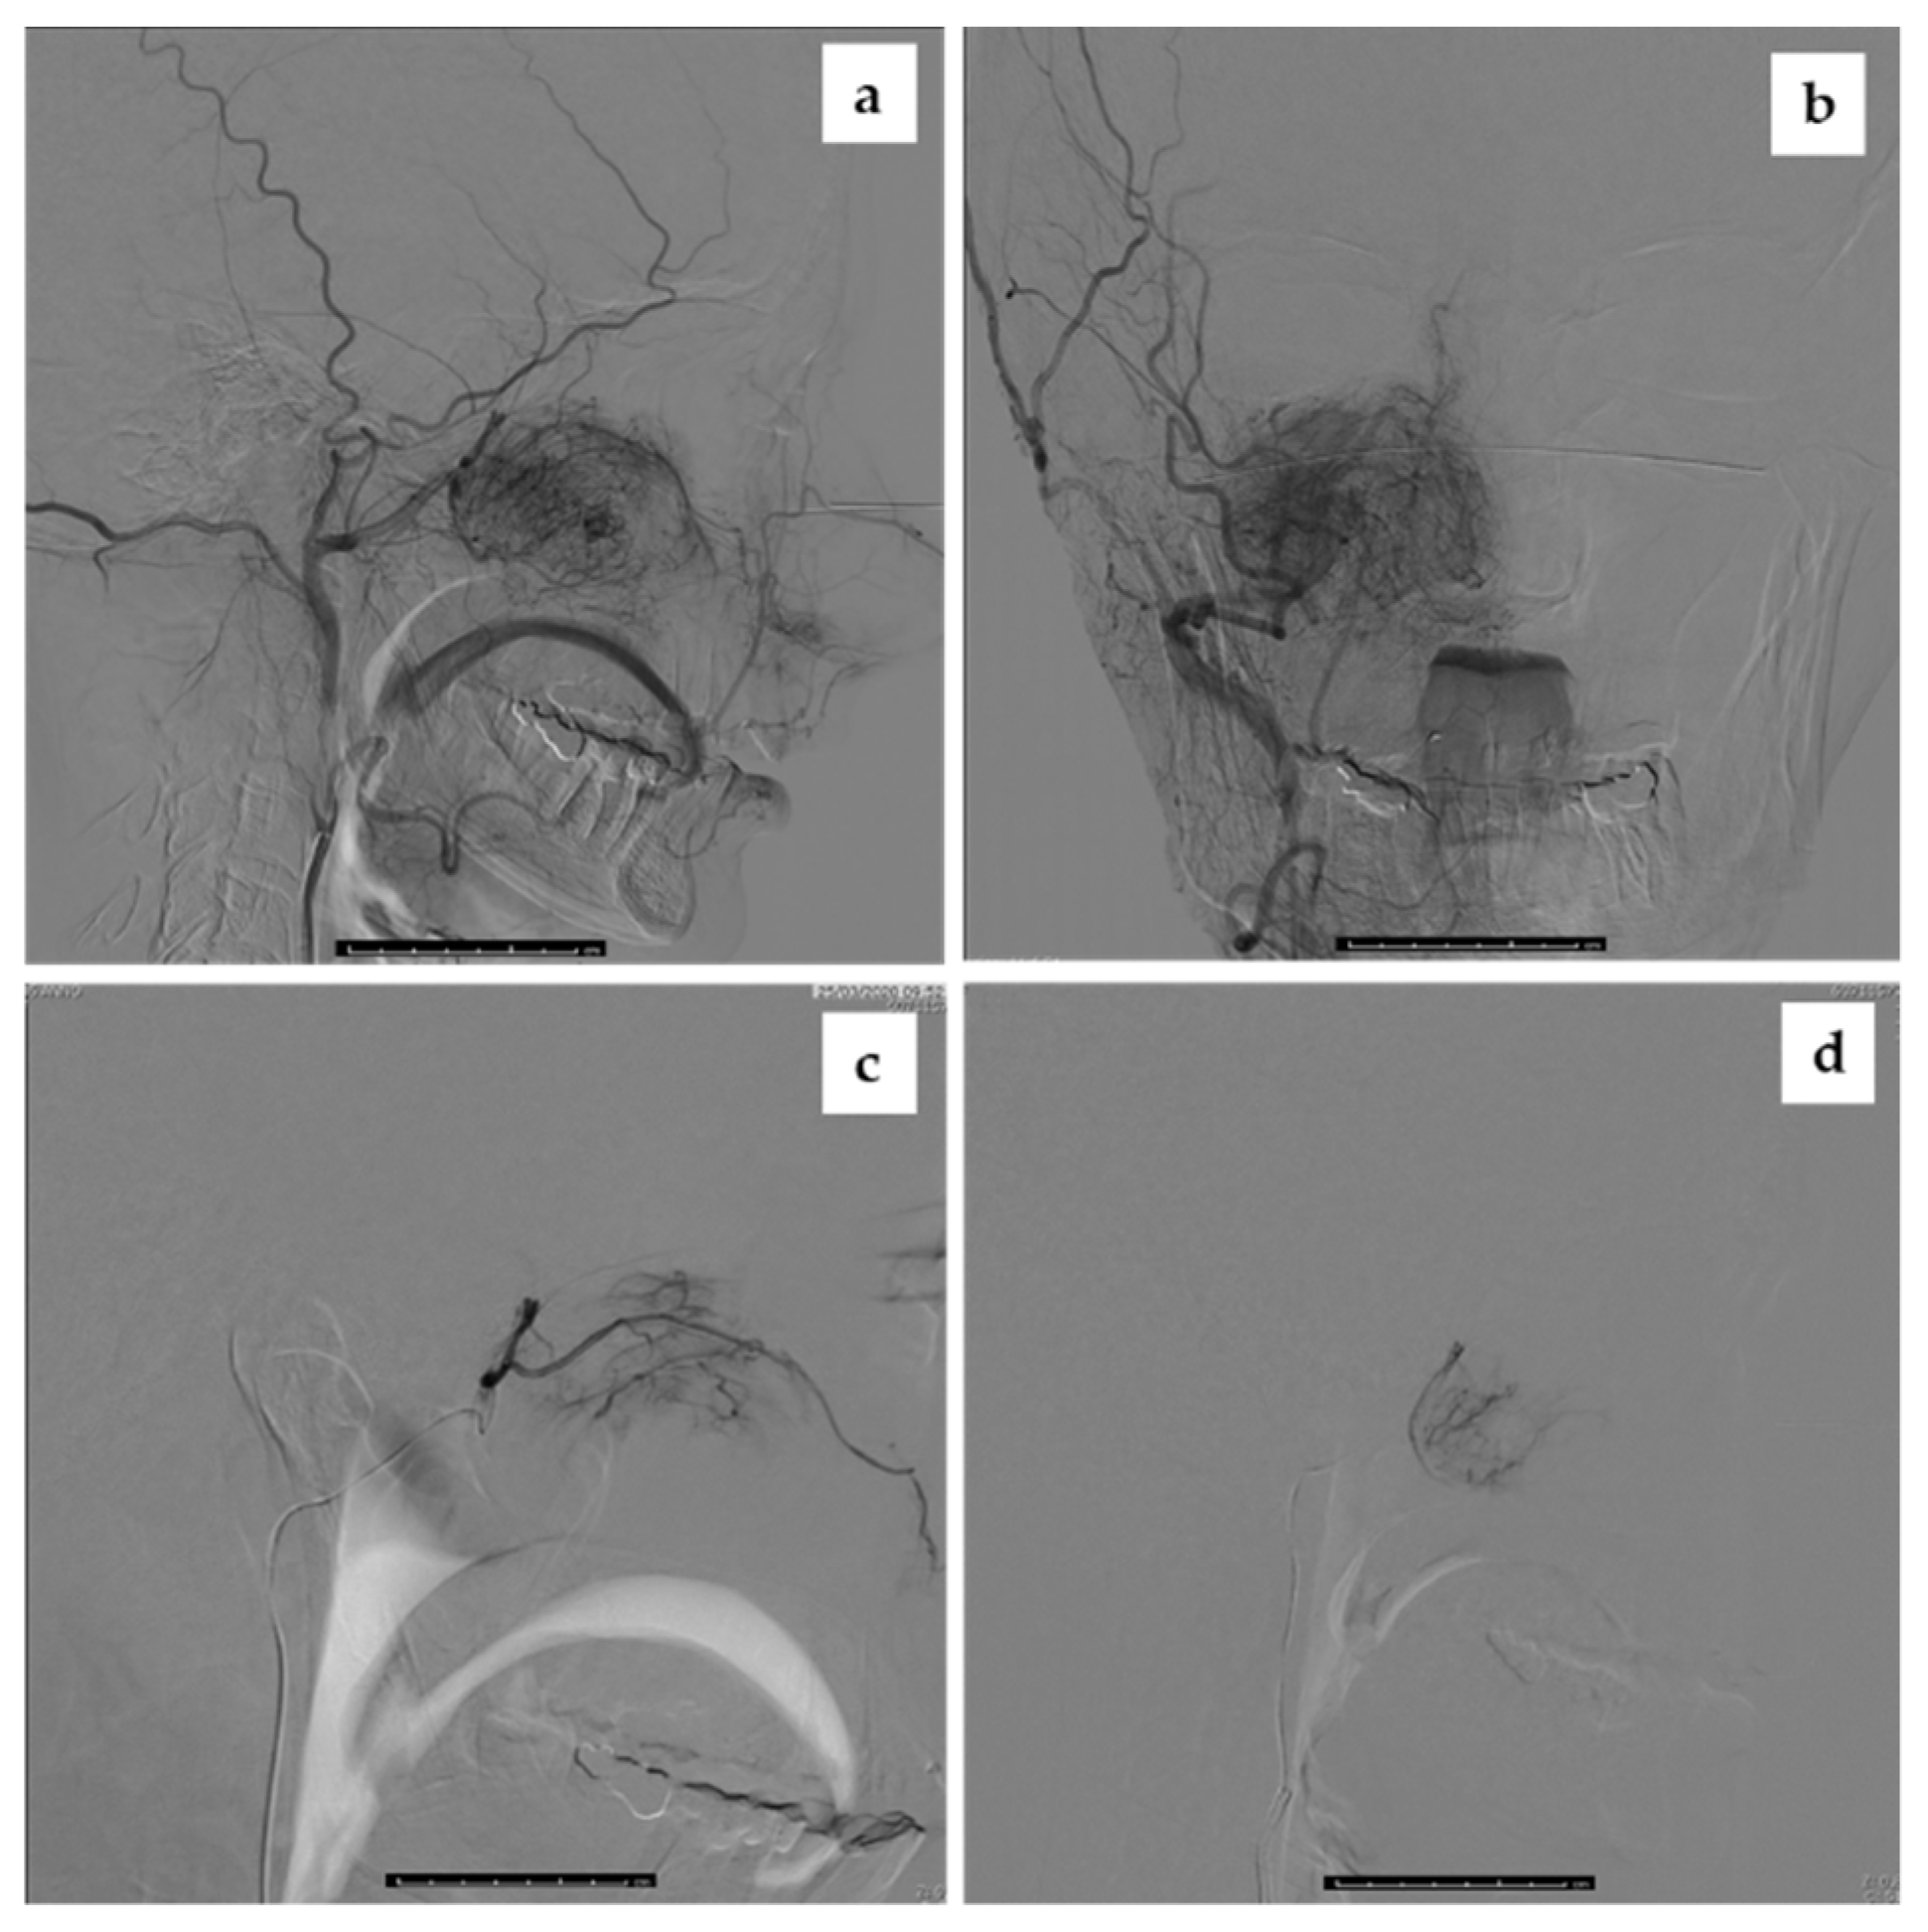

2.3. Intraoperative Imaging and Embolization Procedure